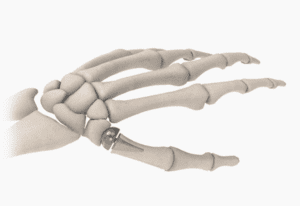

Common Conditions of the Thumb

Basal Joint Arthritis Thumb arthritis is the most common form…